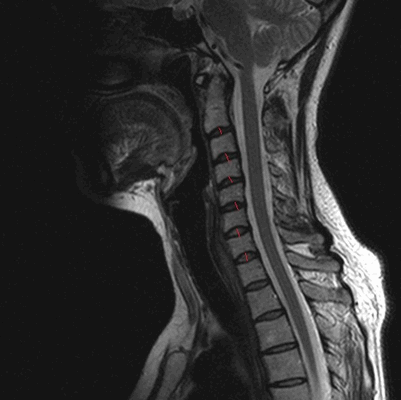

МРТ позвоночника в шейном отделе, оценка высоты дисков (указана красными линиями)

Среди всех заболеваний опорно-двигательного аппарата лидируют патологии позвоночного столба. Вариативность проявлений затрудняет диагностику. Чтобы правильно определить болезнь, врачам необходимо изучить структуру костей и мягких тканей позвоночника. Часто с указанной целью применяют визуализационные методы диагностики — рентгенографию и МР-сканирование. Однако исследования нельзя назвать взаимозаменяемыми. Что лучше, рентген или МРТ позвоночника, определяет врач, исходя из клинической ситуации и целей, поставленных перед диагностикой. По описанной выше причине нельзя проводить какое-либо исследование по собственной инициативе или самостоятельно заменять назначенную доктором процедуру.